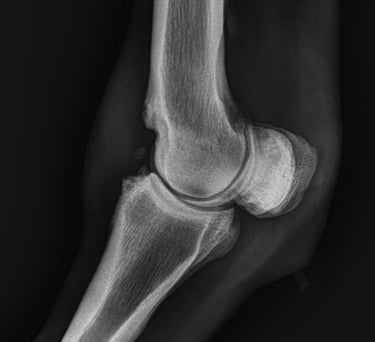

DIAGNOSTICO POR IMAGENES: ECOGRAFIA Y RADIOGRAFIA